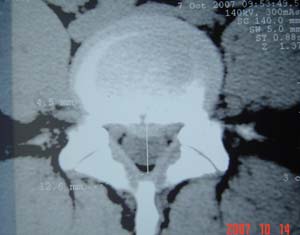

本人的片子,腰腿痛多年,时轻时重。请各位老师发表高见!

1.l4~5间盘膨出伴突出(中央型)

2.l5-s1后纵韧带钙化.

测量应该测上一层面,。支持诊断。